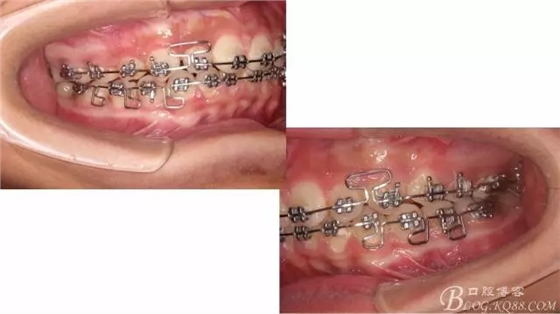

佩戴三個(gè)月的FR2, 效果奇佳!前牙基本達(dá)到淺覆蓋,淺覆合!接下來進(jìn)入二期直絲弓固定正畸,排齊階段!

接下來盡管配合些雙側(cè)后牙對(duì)角牽引,咬合關(guān)系依,不盡人意。

640.webp (11).jpg

640.webp (12).jpg

640.webp (13).jpg

下頜配合多曲方絲,三角牽引,調(diào)整咬合。